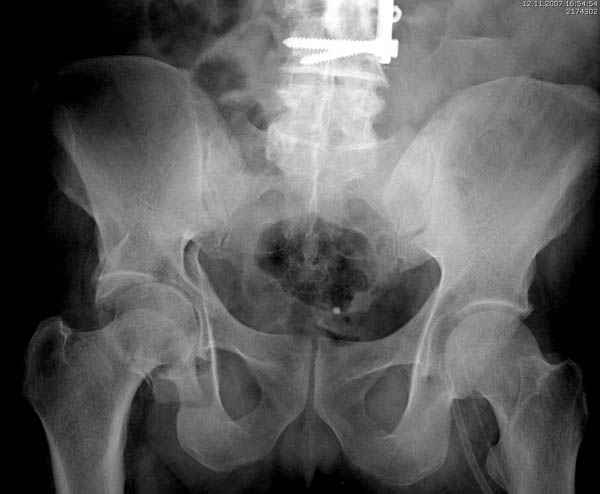

Кроме перелома плеча у больного старый дистракционный перелом T12-L1 оперированный когда-то и кем-то, открытый перелом костей предплечья, который был прооперирован в ночь поступления, после I&D (хирургической обработки). Из-за разрыва селезенки при поступлении травма хирургами произведено удаление.

Дополнительно имеется перелом ацетабулума: задняя

колонна с полупоперечным переломом, и переломы костей лица.

На седьмой день зафиксирован перелом ацетабулума через задний доступ. Перед операцией для профилактики DVT, IVC фильтер, также получает Lovenox.

Извиняюсь за качества снимков, обычный больной в 300 фунтов, портативным ренген аппаратом не пробить.